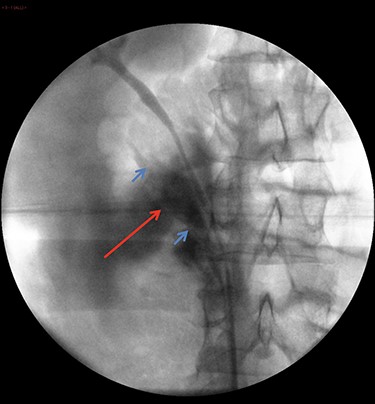

On arrival at 02:00, her temperature was 40.3°C with stable vital signs. After assessment by a multidisciplinary trauma team (orthopaedics, general surgery and urology), she had a CT Urogram that showed duplex kidneys and extravasation of contrast within the right peritoneum in keeping with urine leak (Figs 1 and 2). The lower moiety ureter was discontinuous with a mildly thickened and hyper-enhancing wall. The area of discontinuity was related to the highest density fluid on urographic phase, in keeping with this being the source of urine leak. The right upper moiety ureter appeared to be intact. There was no concomitant parenchymal injury.

CT Urogram demonstrating extravasation of contrast. The blue arrows show the severed ends of the right inferior collecting system. The red arrow shows the contrast extravasation.